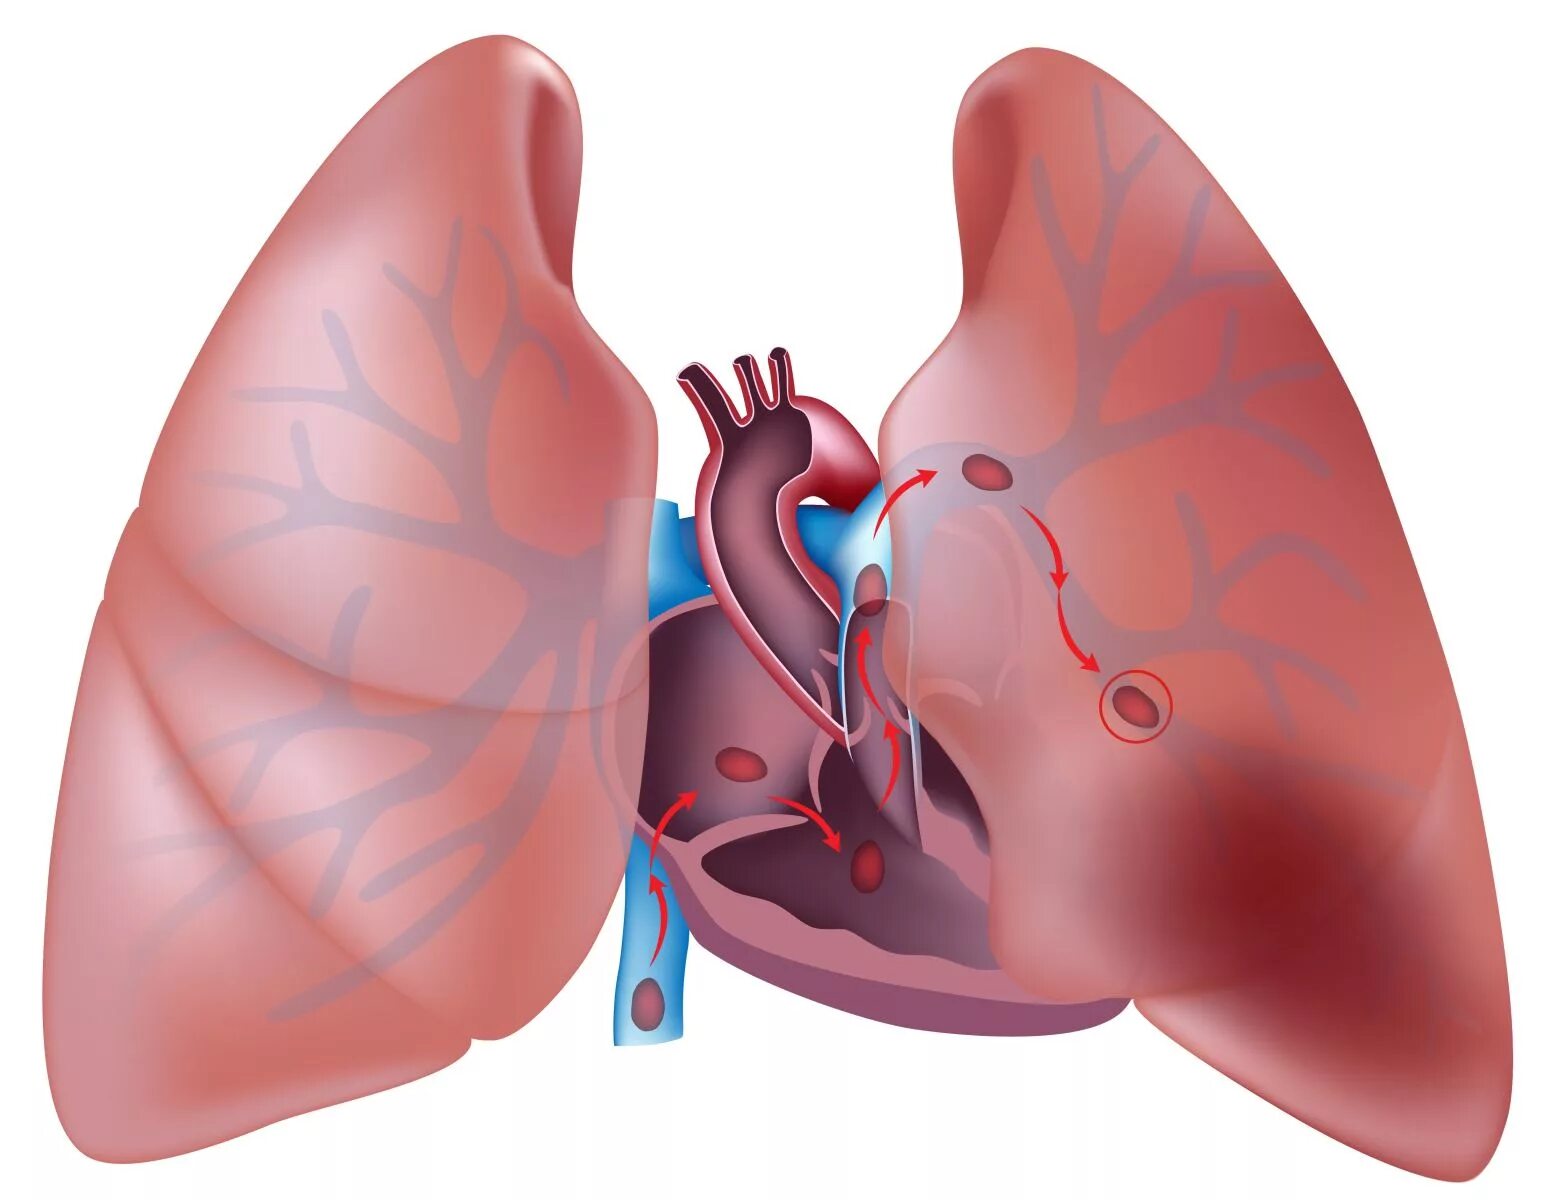

Скате легких